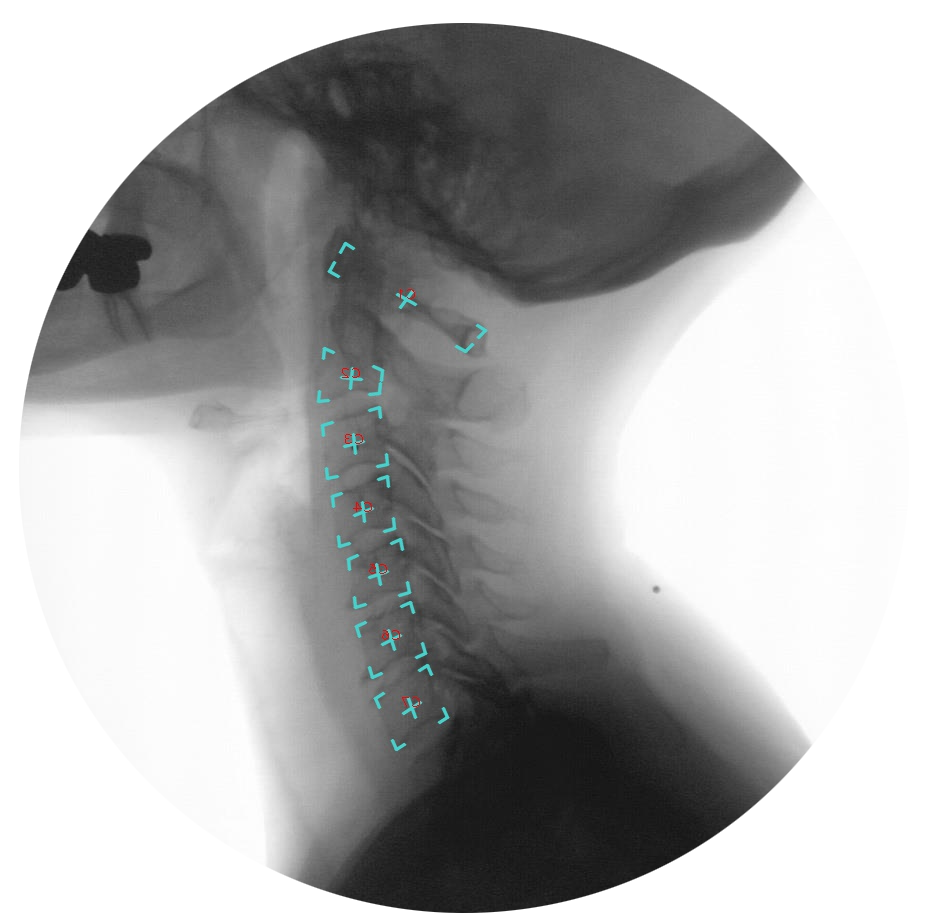

This scan provides real-time guided motion imaging in the upper spine and neck, offering valuable insights into spinal function and mobility.

Unlike traditional X-rays, MRI and CT scans that only provide a snapshot of the spine in a fixed position, digital motion X-ray (DMX), or videofluoroscopy, produces a video of the neck with less radiation. This way, you can see how your discs, bones and ligaments go through a full range of motion in real time.

You simply stand or sit in an upright position in a large, open machine, and it slowly guides you through the appropriate motions, taking video in real-time. Using a proprietary software system, physicians then analyze the data to check for instability, misalignment, and abnormal vertebral motion.

They can also see ligament laxity. This is how loose or flexible your tissue bands are that connect bones at the joints. If they are too loose or flexible, this can lead to joint mobility, instability and more issues.